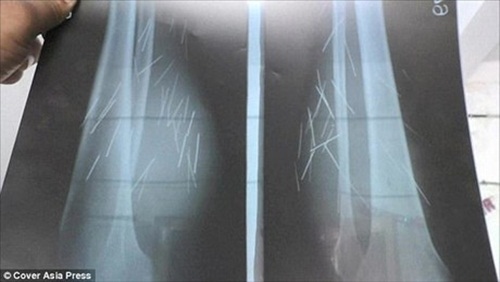

Các bác sĩ đã tiến hành chụp X-quang và phát hiện ra hơn 70 vật thể kim loại bên trong chân của người phụ nữ 35 tuổi.

Sau rất nhiều lần tìm kiếm sự giúp đỡ của các bệnh viện, cuối cùng cũng có một bệnh viện đồng ý điều trị cho cô. Anusuiya đến bệnh viện quận Fatehpur vào ngày 25/10. Tại đây, các bác sĩ đã chụp X quang và phát hiện hơn 70 vật thể kim loại bên trong chân của cô.

Tiến sĩ Naresh Vishal, bác sĩ tại bệnh viện nơi Anusuiya điều trị, cho biết, toàn bộ số đinh đều chỉ tập chung ở phần chân của Anusuiya.